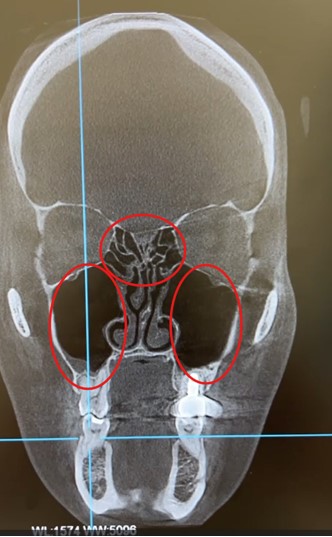

Через 10 дней после начала лечения (третий прием) пациентка активных жалоб не предъявляла. Контрольная КТ показала, что все пазухи полностью пневматизированы (свободны от патологического содержимого). В диагнозе было констатировано выздоровление после острого пансинусита и хронического полипозного риносинусита.